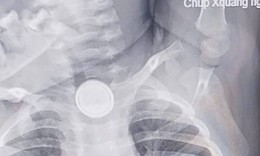

Nội soi gắp dị vật là vòng bạc trong dạ dày bé gái 5 tuổi

Y tế - 09/10/2025 18:30SKĐS - Mới đây, Bệnh viện Việt Nam – Thụy Điển Uông Bí tiếp nhận và xử trí thành công trường hợp trẻ 5 tuổi nuốt phải dị vật là chiếc vòng tay bằng bạc, dài khoảng 7 cm.